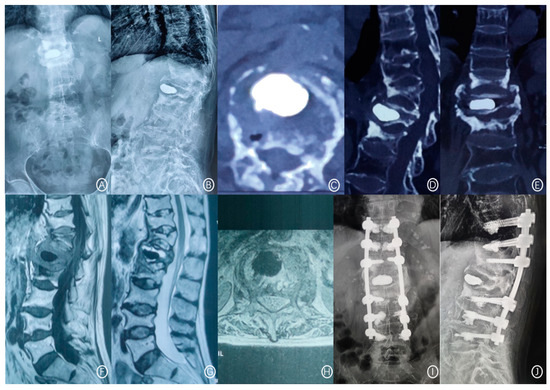

Figure 2.

A 71-year-old female patient had recurrent low back pain and limited movement 3 years after L1 vertebroplasty. (A,B): Lumbar positive and lateral X-ray films scanning at 36 months after PVP showed L1 vertebral cement displacement and T12 vertebral compression fracture. (C–E): CT cross-section, sagittal plane, and coronal plane showed anterior cortex defect and bone cement displacement of the L1 vertebral body and compression fracture of the T12 vertebral body. (F–H): T1W1 showed low signal intensity, and T2W1 showed high signal intensity at the L1 vertebral body. (I,J): The positive and lateral positions of X-ray films showed that after posterior thoracolumbar bone graft fusion and bone cement enhanced internal fixation.